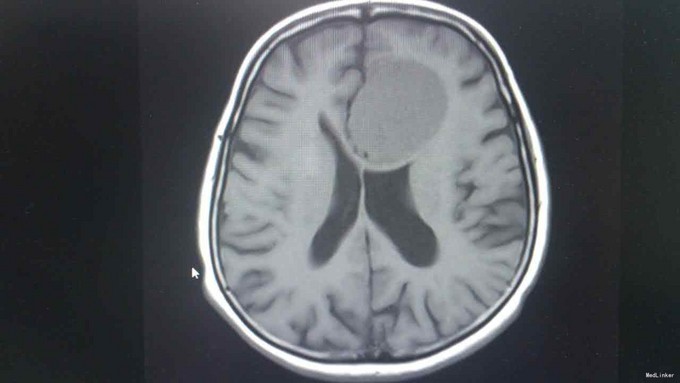

T:37℃,R: 20次/分,P:84次/分,BP:122/88mmHg。发育正常,营养中等,自主体位,步态平稳,表情自如,神志清楚,对答切题,查体合作。皮肤粘膜未见苍白、黄染,未见皮疹,无皮下出血点,无伤口。全身浅表淋巴结未扪及肿大。头颅无畸形。眉毛无脱落,眼睑无水肿、下垂、倒睫,睑结膜无苍白、充血,球结膜无充血、水肿,巩膜无黄染,角膜透明,眼球活动灵活,无凸出、凹陷、震颤、运动障碍,双侧瞳孔等大等圆,直径约3mm,对光反射灵敏,集合反射正常,左眼不能正常闭合。耳廓正常,无畸形,鼻部外形无异常,口唇红润,口腔粘膜未见出血点及溃疡,伸舌左偏,咽部无充血,扁桃体无肿大。颈软,无抵抗,颈静脉无充盈,肝颈静脉回流征(-),气管居中,甲状腺不大。胸廓对称无畸形、无局部膨隆或凹陷。呼吸平稳,节律规则。双侧呼吸动度对称。双肺部叩诊清音。双肺呼吸音清,未闻及干湿性啰音。心界不大,心率84次/分,律齐,各瓣膜区未闻及病理性杂音。腹平软,未及压痛,未及反跳痛,腹部未扪及包块,肝右肋下、剑突下未及,脾未触及,胆囊未触及,Murphy征(-)。移动性浊音阴性,肠鸣音正常,约4次/分。脊柱四肢无异常。生理反射存在,病理反射未引出。 专科检查:计算力、定向力、记忆力正常,双侧瞳孔等大等圆,直径约 4mm,对光反射灵敏,辐辏反射正常,眼球运动无受限,左侧眼睛不能正常闭合,左侧额纹消失,左侧鼻唇沟变浅,伸舌左偏,鼓腮无漏气,双上肢肌力5级,双下肢肌力5级,生理反射存在,病理反射未引出。 相关检查:血常规、大便常规、肝功能、凝血四项、离子四项、心肌酶、血脂四项、肾功能、肿瘤二项未见明显异常。 头颅增强MR1.左侧额叶大脑镰旁见团块状异常信号影,考虑脑膜瘤;2.双侧辐射冠区缺血灶;3.轻度脑萎缩。 肝胆脾胰B超、泌尿系B超未见异常。胸片示:1.双肺纹理稍增多、增粗,请结合临床;2.右上纵隔增宽,建议必要时CT检查。

诊断:脑膜瘤 治疗:甘露醇、地塞米松降颅压,择期手术治疗。

中枢性面瘫及周围性面瘫要注意鉴别,本病例患者中枢性体征不明显,急诊科有误诊,入院后完善相关检查才明确。如果按照周围性面瘫治疗必然会延误病情。